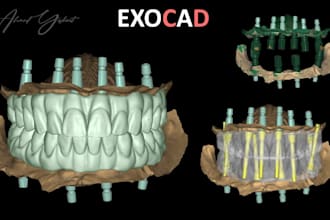

I will do dental prosthesis crown design using exocad, 3shape, inlab and cerec

From $20